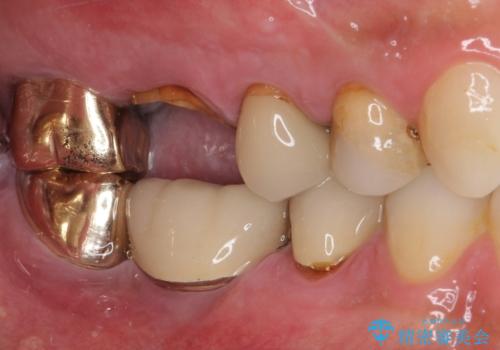

左側は大臼歯2本と小臼歯1本が欠損しているため、インプラント2本を治療したブリッジ、右側は中間欠損であり、前後の歯も加療が必要であったためブリッジによる補綴治療を行うこととしました。

抜歯となった歯は全て神経が抜かれた歯であり、強大な咬合力によって破折したことが原因で抜歯となりました。

左右同時に強大な力を受けながらの治療であったため、仮歯の脱落や破損などがひんぱつしました。